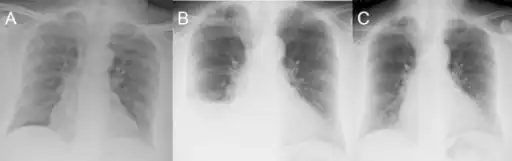

Olanzapine-induced eosinophilic pleuritis;a)Prior to olanzapine therapy, b) CXR at presentation, c) CXR 6 months after olanzapine withdrawal. -

Pleural biopsy demonstrates a chronic inflammatory cell infiltrate and eosinophils induced via olanzapine